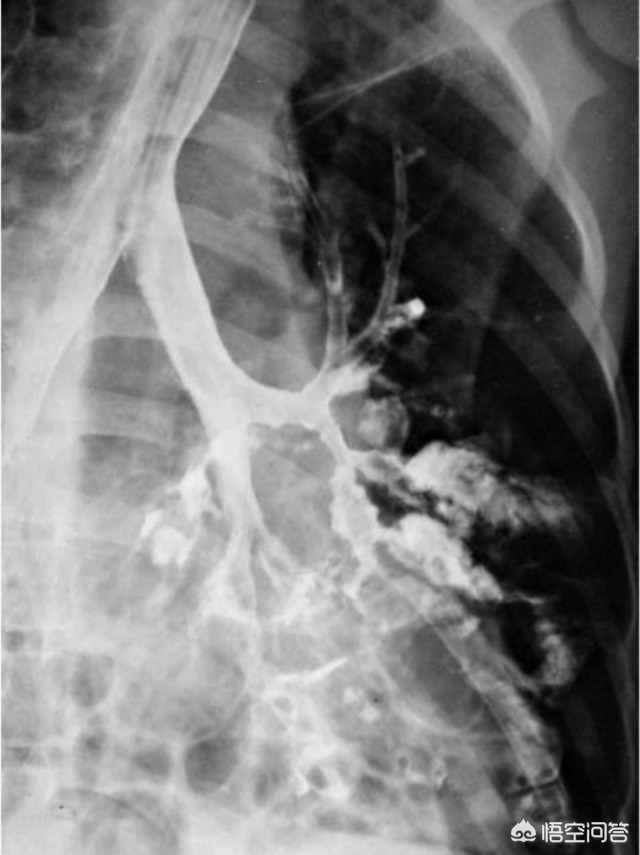

支气管扩张的诊断,X线检查有重要意义,支气管造影术可确诊,能明确支气管扩张的部位、性质和范围,为手术切除提供重要的资料。对造影剂过敏者可做胸部CT检查,超薄CT扫描是诊断支气管扩张的一项敏感检查方法。

在CT没有广泛应用前,要诊断支扩,得做支气管造影。往支气管内打一种碘油,等到碘油涂抹到支气管管壁上后,拍X线片,这时支气管是显影的,可以根据其情况判断有无支扩,支扩的部位等,病人及其痛苦。